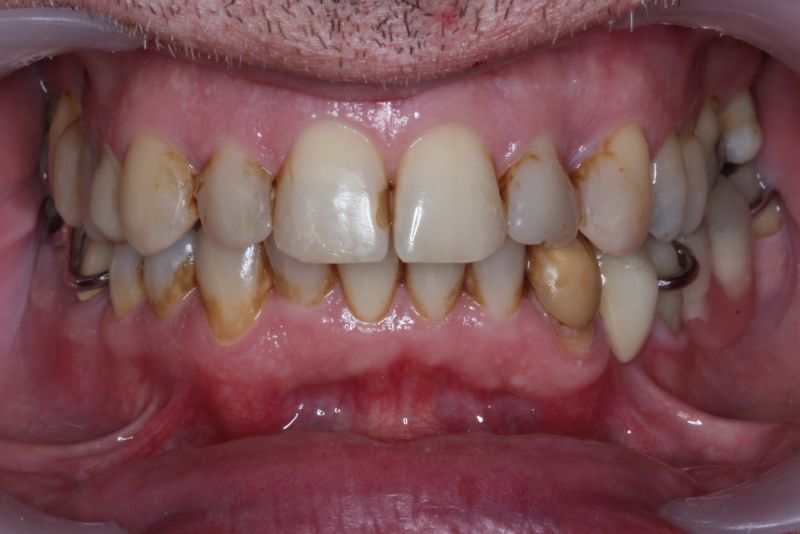

Erkennbar ist die massive Abweichung der habituellen Bisslage von der neuromuskulär zentrierten Bisslage.